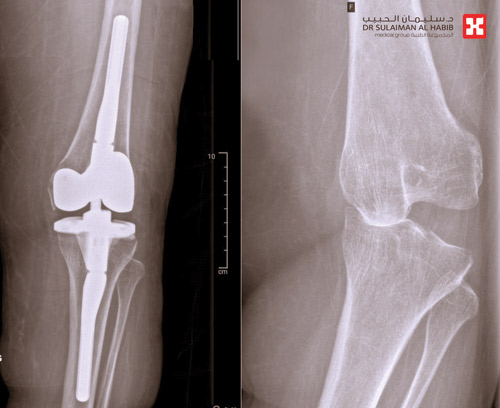

نجح مستشفى الدكتور سليمان الحبيب بالقصيم بفضل الله عز وجل عبر فريق طبي متخصص في زراعة المفاصل، بإجراء عملية لتركيب مفصل صناعي بالركبة اليسرى لمريضة في العقد السادس من عمرها استعادت بعدها القدرة على المشي. ذكر ذلك الدكتور علاء محمد حمدان استشاري جراحة العظام والمفاصل رئيس الفريق الطبي المعالج. الذي أضاف بأن المريضة وصلت للعيادة على كرسي متحرك ولا تستطيع المشي، وعند سماع شكواها وتاريخها المرضي، تبين أنها تعاني من شلل أطفال كامل منذ الصغر في الطرف السفلي الأيمن وشلل جزئي بالطرف الأيسر. وأشار إلى أن الفحص السريري للمريضة أبان عدم قدرتها على الوقوف نهائياً، وأنها كانت قبل 10 سنوات مضت تسعى للمشي والحركة من خلال الضغط على الجهة اليسرى ولم تستطع ذلك، مع العلم بأن لديها جهازاً خاصاً مثبتٌ في الركبة اليمنى للمساعدة في عملية التوازن. وقد تم إخضاع المريضة لعدد من الفحوصات بالأشعة السينية الرقمية (Digital X-rays) والتحاليل المخبرية ، وقد أوضحت النتائج بدقة وجود احتكاك شديد جداً في الركبة اليسرى من الدرجة الرابعة مع ارتخاء بالأربطة وعدم الثبات.

وبعد اطلاع الفريق الطبي المعالج على كامل النتائج والفحوصات، قرر التدخل الجراحي لعلاج المريضة، مشيراً إلى أن العملية استغرقت ساعتين تحت التخدير الكلي، وتم فيها إزالة مفصل الركبة الأيسر القديم واستبداله بآخر متطور، يتيح الحركة للمريضة بشكل جيد وبثبات عالٍ.